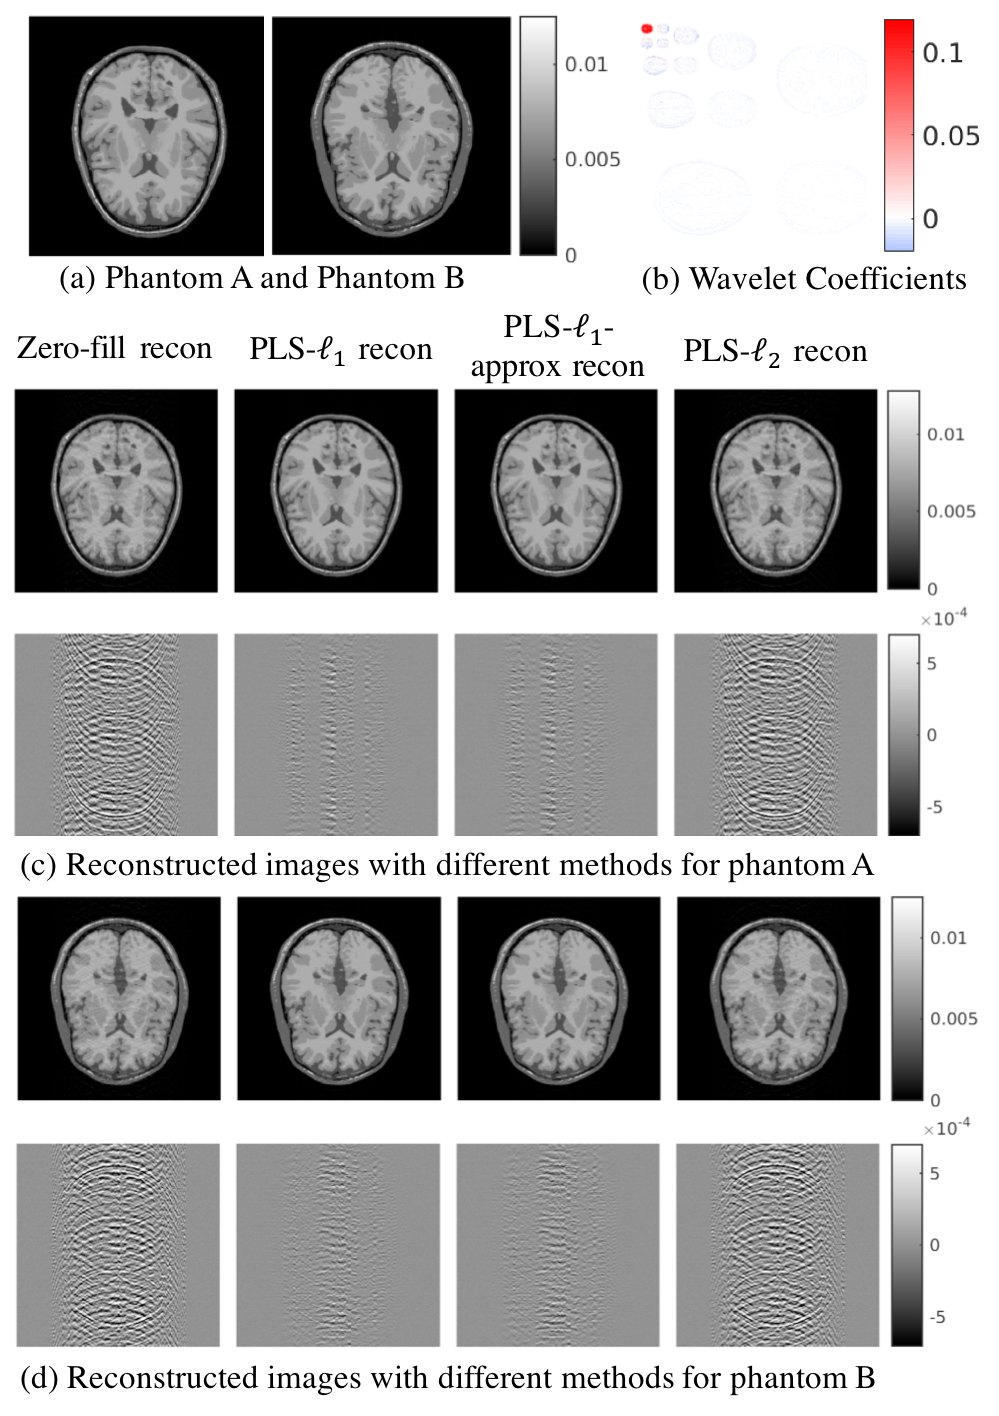

Refer to caption

Figure 3: The reconstructed images for two different phantoms (shown in (a)) and different reconstruction methods. Subfigure (b) shows the wavelet coefficients for the first phantom. Zeros are denoted by the white color. The widespread white region in the wavelet image demonstrates the sparseness in the wavelet domain. Subfigures (c) and (d) show reconstructed images for the two different phantoms. In both (c) and (d), the first row shows the reconstructed images and the second row shows the difference images between the reconstructed images and the true phantom. In each row, from left to right are zero-filling reconstruction, PLS-1subscript1\ell_{1} reconstruction, PLS-1approxsubscript1𝑎𝑝𝑝𝑟𝑜𝑥\ell_{1}-approx reconstruction, and PLS-2subscript2\ell_{2} reconstruction.

The estimates above were computed from computer-simulated data corresponding to a stylized two-dimensional (2D) MRI example in which the imaging system sampled random lines from k-space. Two different head phantoms were employed to represent the to-be-imaged object, which are displayed in Figs. 3-(a). The sparsity of the phantom in the wavelet domain is demonstrated in Figs. 3-(b). Additional details regarding these numerical phantoms are described later in Sec. V-A. To demonstrate the impact of under-sampling in the simulated measurement data, images were reconstructed by zero-filling the missing k-space regions and applying an inverse 2D discrete Fourier transform (DFT). This method is also known as the pseudoinverse method [18]. The resulting images, shown in the first rows and second columns of Figs. 3-(c) and (d), contain aliasing artifacts. The artifacts are clearly visible in the difference images that are shown in the second rows and first columns of Figs. 3-(c) and (d), which were formed by subtracting the reconstructed images from the corresponding true phantoms.

The images corresponding to the PLS-1subscript1\ell_{1}, PLS-1approxsubscript1𝑎𝑝𝑝𝑟𝑜𝑥\ell_{1}-approx, and PLS-2subscript2\ell_{2} estimates are displayed in the second, third, and fourth columns of the top rows in Figs. 3-(c) and (d). The corresponding difference images are shown in the lower row of each subfigure. Note that the PLS-2subscript2\ell_{2} estimate contains significant artifacts that are similar in nature to those produced by the zero-filling-inverse DFT approach. Tuning the regularization parameter did not change this observation. On the other hand, the PLS-1subscript1\ell_{1} and PLS-1approxsubscript1𝑎𝑝𝑝𝑟𝑜𝑥\ell_{1}-approx estimates have significantly reduced artifact levels as compared to the PLS-2subscript2\ell_{2} estimate. This is expected, as sparsity-promoting regularization methods are known to be more effective for mitigating data incompleteness than 2subscript2\ell_{2}-based methods. Moreover, it is observed that the PLS-1subscript1\ell_{1} and PLS-1approxsubscript1𝑎𝑝𝑝𝑟𝑜𝑥\ell_{1}-approx image estimates are nearly indistinguishable. Namely, the magnitude and spatial distribution of errors in these two image estimates, as reflected in the difference images, are almost the same. This suggests that the approximated prior in Eq. (14) promotes (wavelet-domain) sparsity is a manner very similar to how the exact sparse prior Eq. (7) does. This is evidence of the accuracy of the variational approximation that underlies the proposed method for computing the SDO test statistic.